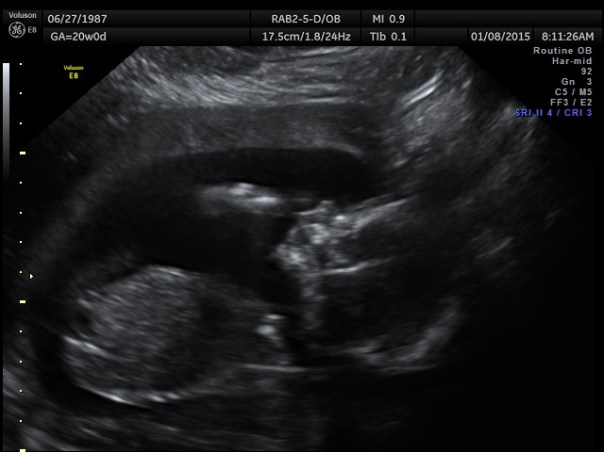

Written January 8. 20 weeks… Halfway to meeting Baby Romenesko!

This morning we had our 20 week appointment — the ULTRASOUND.

What we do know is that we have a really active baby! Twisting and turning, moving all over the place! The appointment took a little longer than it should have because the baby just wouldn’t hold still for all of the measurements to be taken. The tech got everything she needed though, and the baby looks fabulous. Measuring right where it should be, due date is still the end of May, and average in size etc. Woohoo!

There’s our baby. Waving hello to the world.